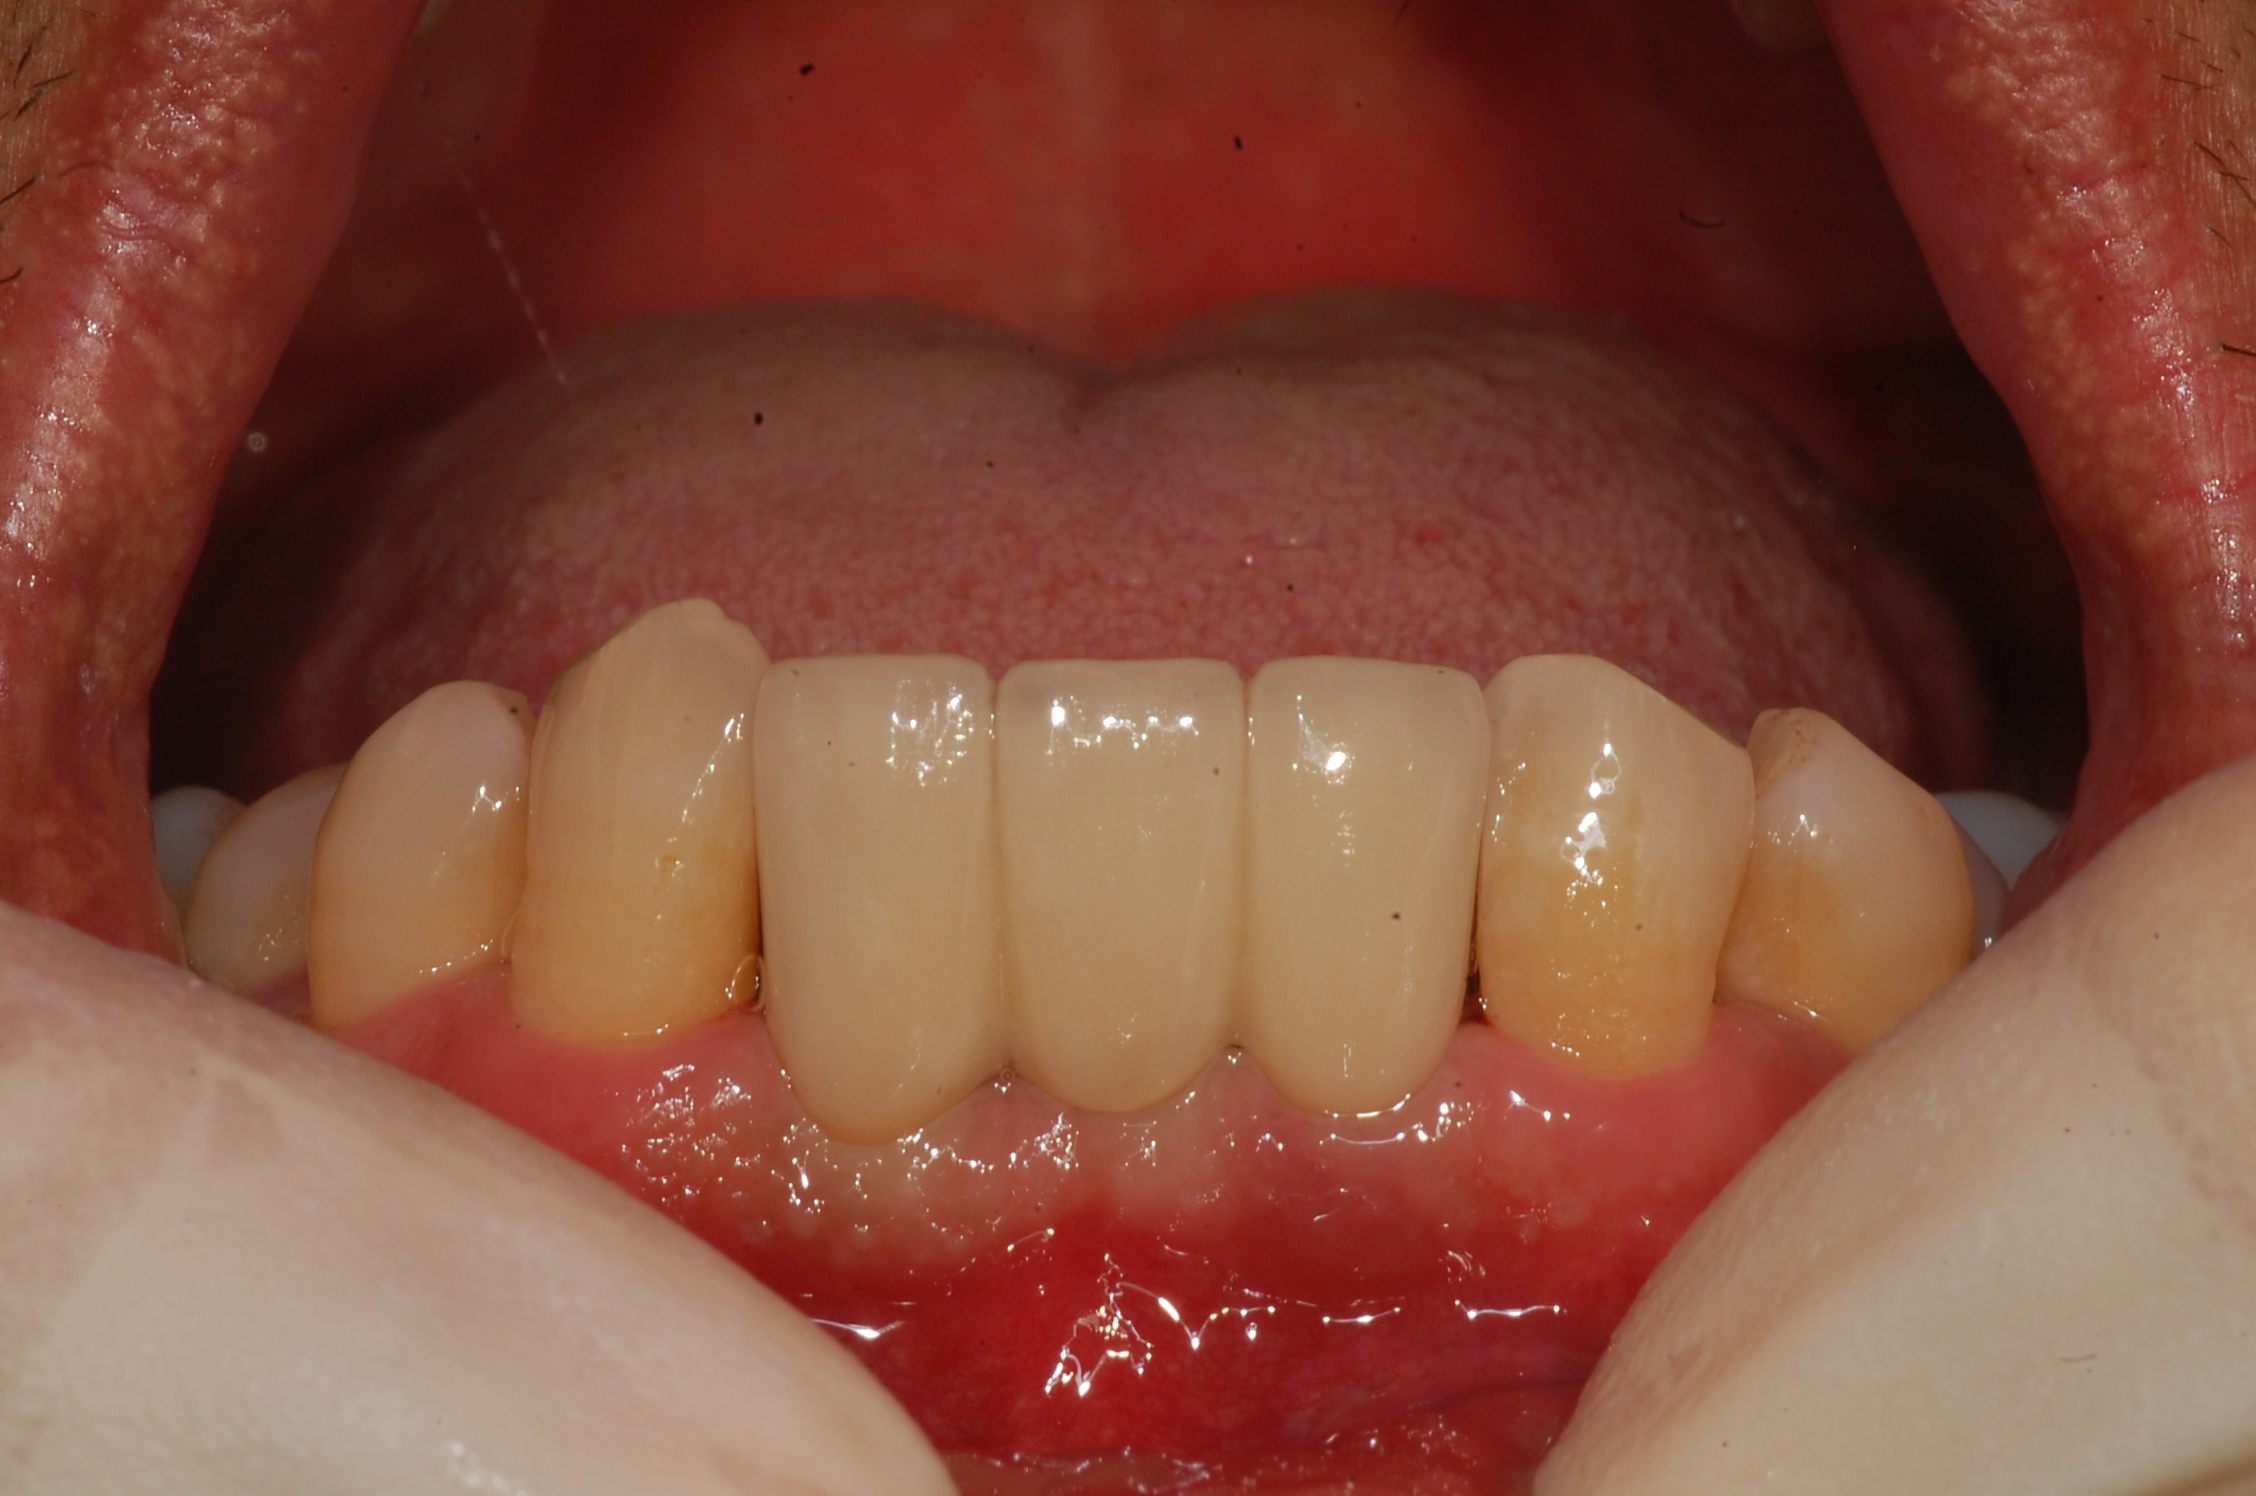

[임플란트] 제목 : 아래 앞니 임플란트

치주질환으로 발치 후 치료